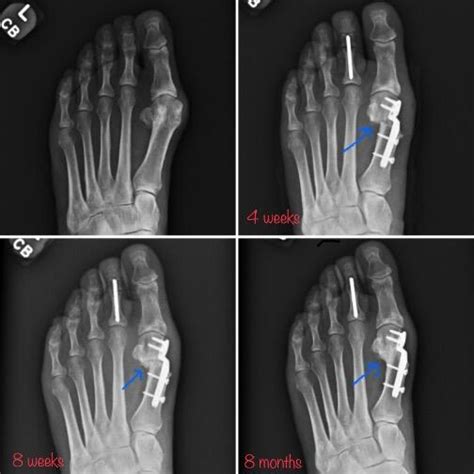

- Bunion (Vbočený palec): Deformita, pri ktorej dochádza k vychýleniu palca smerom k ostatným prstom a zároveň k vyklenutiu kosti na vnútornej strane chodidla. Táto deformita spôsobuje bolesť, zápal a podráždenie, najmä pri nosení úzkej obuvi. Nesprávne postavenie palca preťažuje ostatné časti nohy, čo môže viesť k ďalším problémom. V niektorých prípadoch môže byť potrebná chirurgická korekcia bunkovej deformity alebo korekcia vbočeného palca.

Chirurgická liečba: V prípadoch vážnych deformít, zlomenín alebo chronických ochorení, ktoré nereagujú na konzervatívnu liečbu, môže byť nutný chirurgický zákrok. Ten môže zahŕňať korekciu deformity, odstránenie zápalového ložiska alebo stabilizáciu kĺbu.